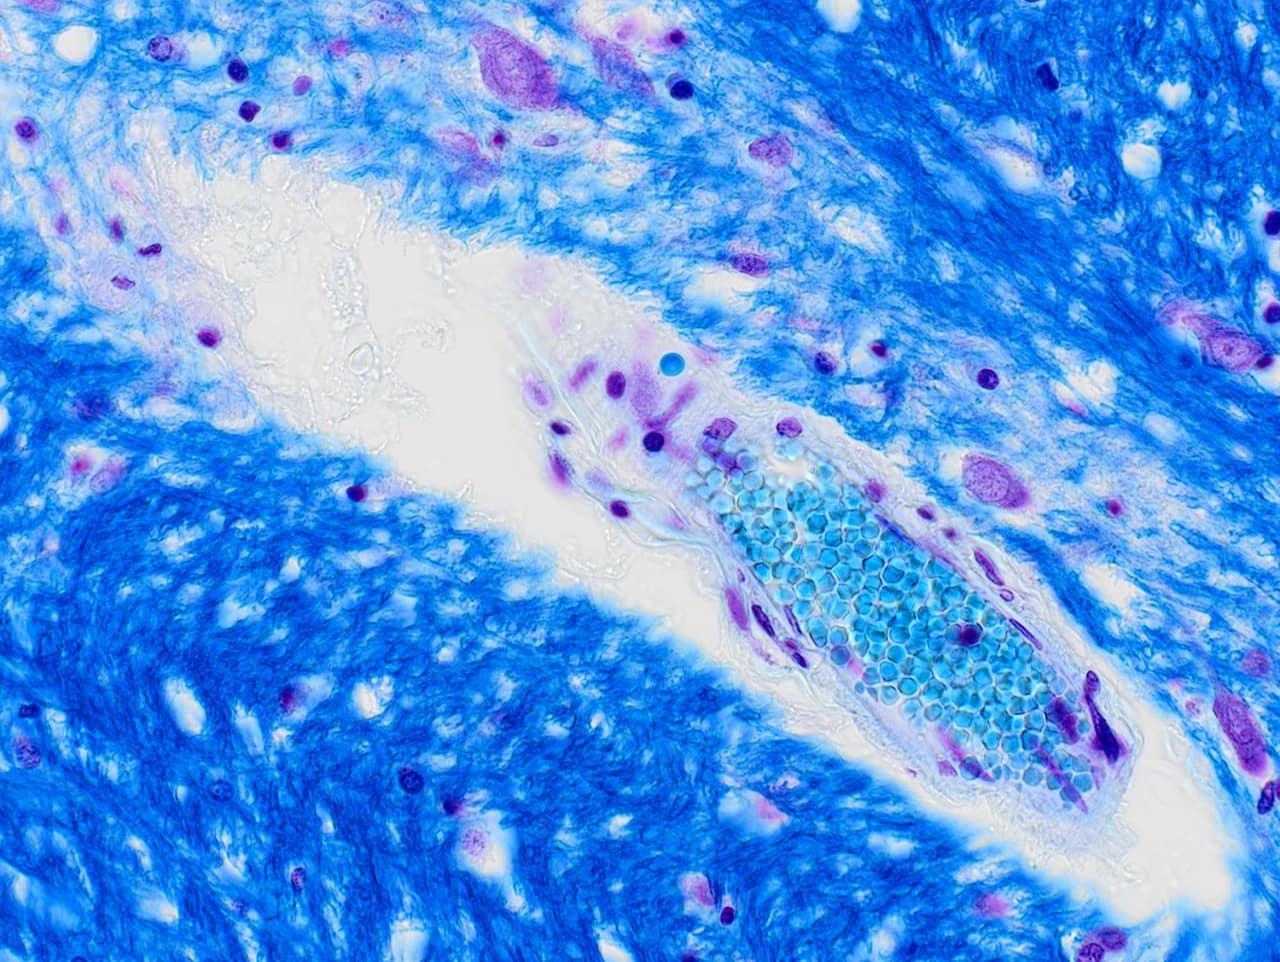

研究人員和病理科醫師常常需要透過顯微鏡檢視各種不同樣本。舉個例子,病理學家使用不同顏色來分辨組織種類,細胞學家則根據柏氏染色(Papanicolaou stain)的顏色差異及型態來進行細胞分類。那麼,如何在顯微影像上重現人眼的彩色視覺呢?首先我們必須暸解一下人眼的彩色視覺以及顯微鏡拍照系統和螢幕的差異性。今天的部落格文章將探討人眼彩色視覺的運作機制並揭示OLYMPUS的照相系統如何將此項技術應用於顯微影像。

大多數相機感測元件的光譜靈敏度都超過700nm,這會使得圖像在紅外光下顯得偏紅。由於人眼看不到近紅外或紅外光,因此我們都會在相機感測元件前加上紅外光濾鏡。接者我們利用顯微影像專門處理技術將感測元件的信號轉換為圖像數據,在電腦螢幕上顯示如同在目鏡底下所見的彩色圖像(圖3)。說比做容易,因為我們必須了解顯微鏡的照明光譜和樣本的光譜特徵,以及各種染料,顏色,照相系統和電腦螢幕的不同特性。利用我們顯微鏡開發以及生物樣本觀察所獲得的知識,我們開發出OLYMPUS獨有的”顯微影像色彩還原技術”,這項技術讓我們能夠提供許多具有絕佳色彩還原能力的顯微照相系統。下次拍照前用用看我們的相機小幫手找出最適合您樣本的照相系統吧!